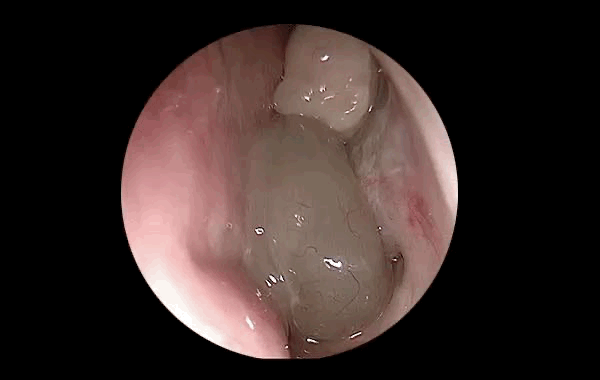

Nazal polipler, burun ve sinüslerin iç yüzeyini kaplayan mukoza dokusunun iltihaplanıp şişmesiyle oluşan yumuşak, iyi huylu şeffaf et büyümeleridir.

Zamanla büyüyerek burun boşluğunu tıkar, nefes almayı zorlaştırır ve sinüslerin hava alışverişini engeller.

•Burun içine yerleştirilen özel endoskopik kamera sayesinde polipler net olarak görüntülenir.